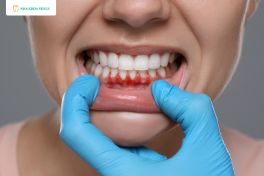

Cạo vôi răng là một bước quan trọng trong việc chăm sóc sức khỏe răng miệng, giúp loại bỏ mảng bám và vôi răng tích tụ trên bề mặt răng và dưới nướu. Quá trình này không chỉ giúp răng sạch sẽ, trắng sáng hơn mà còn ngăn ngừa các bệnh lý nha khoa như viêm nướu, viêm nha chu và sâu răng.

Tại Nha khoa Venus, dịch vụ cạo vôi răng được thực hiện bởi đội ngũ bác sĩ giàu kinh nghiệm, sử dụng thiết bị hiện đại và công nghệ tiên tiến. Quy trình bao gồm các bước: thăm khám và tư vấn, chụp X-Quang và lên phác đồ, tiến hành cạo vôi răng, đánh bóng răng và hoàn thành điều trị. Đặc biệt, khách hàng sẽ luôn cảm thấy thoải mái nhờ kỹ thuật nhẹ nhàng, an toàn và không gây đau nhức.